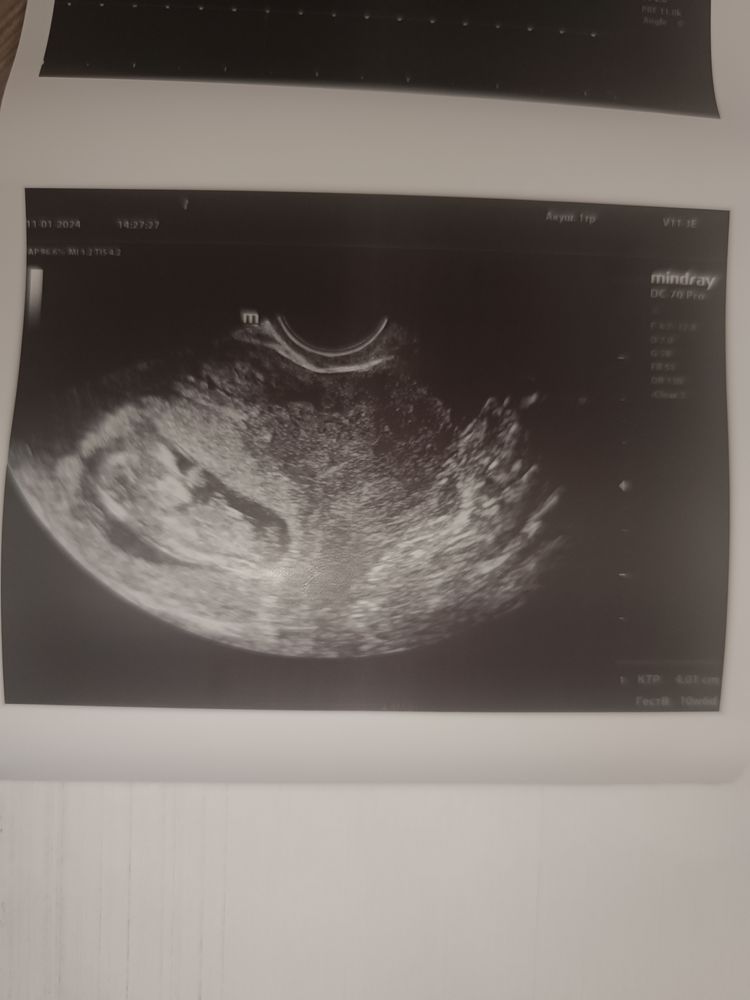

Ждем скрининг!!!

Юлия, все слава богу хорошо,растет и развивается 🥰 теперь тоже жду скрининг!!!

ПЯ 10 мм, жм 3 мм, 4 недели 19 ДПП и кровотечение, ГКБ 31